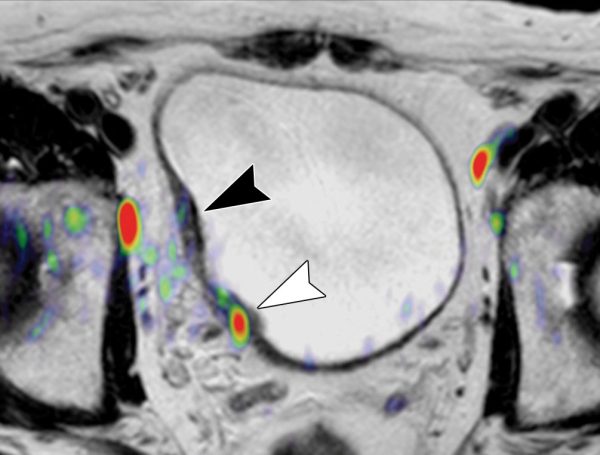

Mesane kanseri ölüm riski taşıyan ciddi bir hastalıktır. Ancak, ölüm riski kanserin evresine, hastanın genel sağlık durumuna ve tedaviye yanıta bağlı olarak değişir. Erken teşhis edilen ve tedavi edilen mesane

Gençlerde mesane kanseri, toplam mesane kanseri vakalarının çok küçük bir kısmını oluşturan, nadir fakat dikkat edilmesi gereken bir sağlık sorunudur. Genellikle 60 yaş üzerindeki bireylerde görülen bu hastalık, 40 yaş